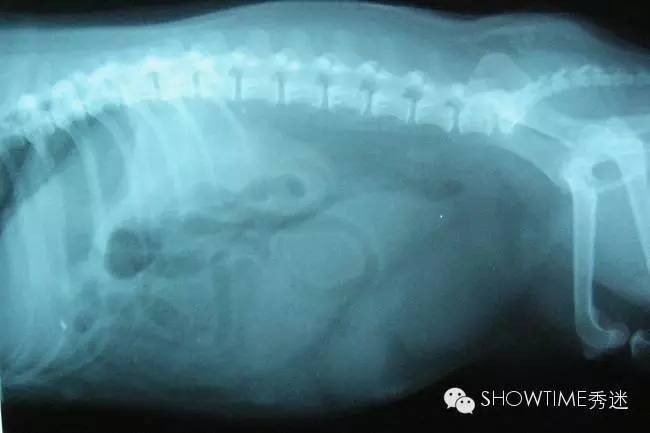

子宫蓄脓症,在宠物医疗方面是一个老生常谈的问题,是母犬疾病中最为常见的一种,近年来,由于子宫蓄脓症导致狗狗死亡的情况时有发生。

与女性相同,母犬的尿道开口在阴道内,泌尿道感染的机率也因此增高。母犬于发情期子宫颈会扩张打开,此时感染源便有机可乘进入子宫内,随着发情期的结束,黄体酮分泌促使子宫颈关闭,并造成子宫内膜对感染源的抵抗力降低,感染源便有机会在密闭的子宫内恣意发展,也就是俗称的“化脓”。而这些脓都是细菌,产生的毒素更能借机有子宫内的血管往身体各部分流窜,进而造成系统性的症状或毒血症。

子宫蓄脓一般分为两大类,开放型和封闭型。

封闭型的症状:(注:封闭型因症状相对不明显,不大容易被察觉)

1、从狗狗的外阴部,看不出黄色粘液状的分泌物,因为脓汁的堆积,堵塞阴部的排泄,这种情况会比较严重,可能引发一系列的并发症,如败血症、内毒血症等等;

4、腹部胀大、严重脱水;

5、情况严重时会出现昏迷、休克等症状,甚至可能直接导致狗狗死亡。